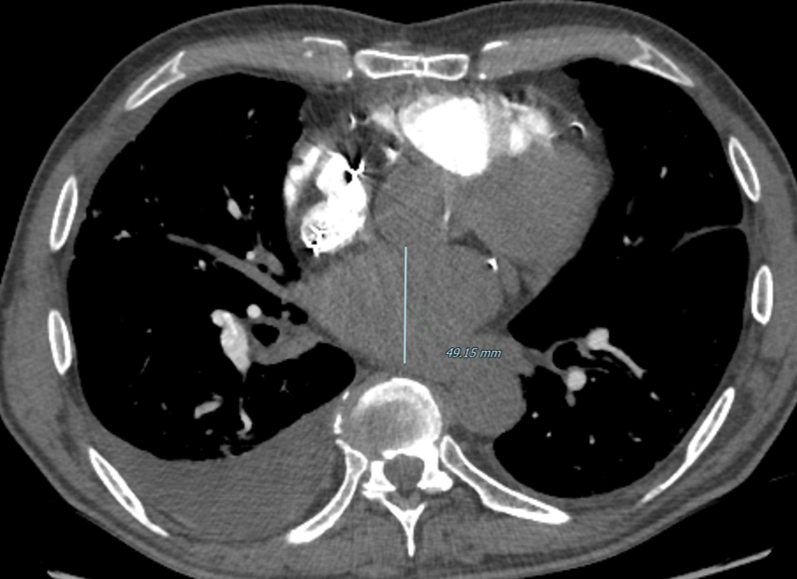

Left atrium enlargement

The diameter measurements of the left atrium on CT axial images should be determined as the largest anterior-posterior diameter. It is a continuous, metric variable.